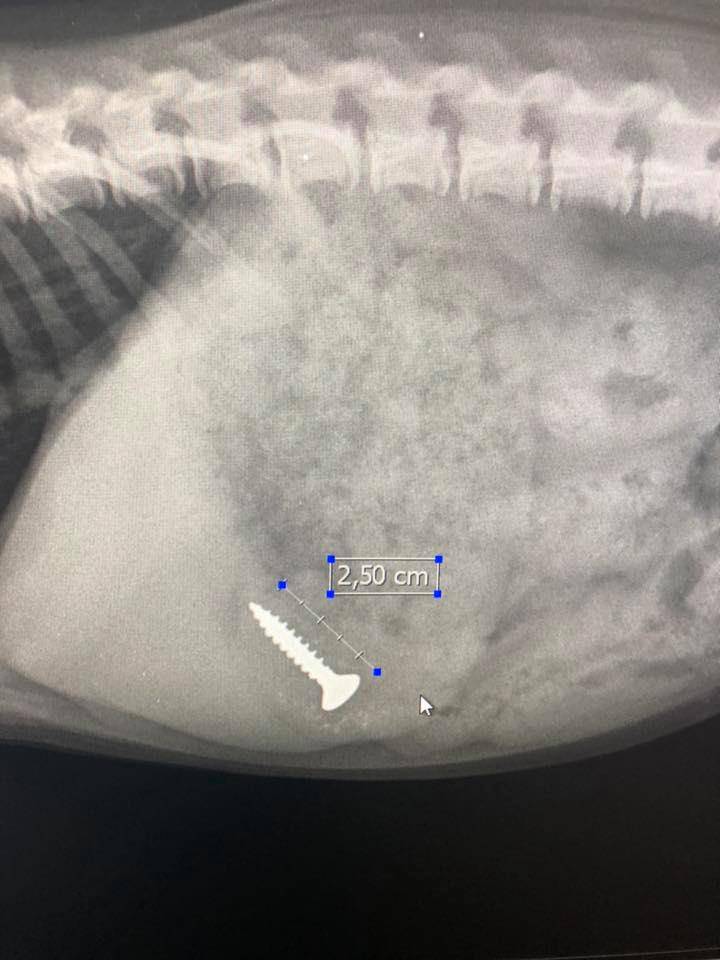

Ponadto zakładamy endoprotezy u psów, które cierpią na dysplazje, zwichnięcie stawów czy złamanie szyi bądź kości udowej.

Założyli mojemu psu endoprotezę. Operacja udana. Psiak znowu cieszy się życiem.